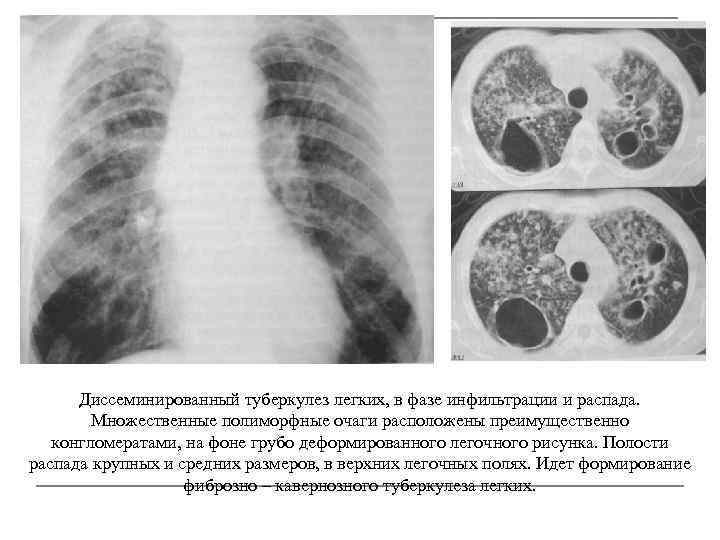

Иллюстрации по теме очагового и инфильтративного туберкулеза